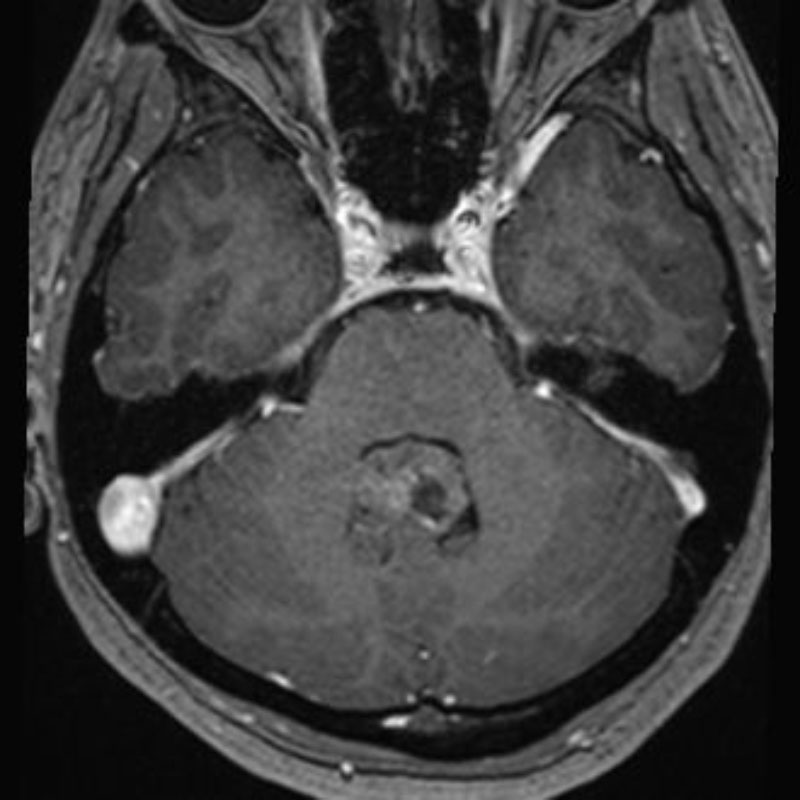

680

'25年10月

30代

小脳腫瘍

頭蓋内腫瘍摘出術

No.’25_82 手術前1

No.’25_82 手術前2